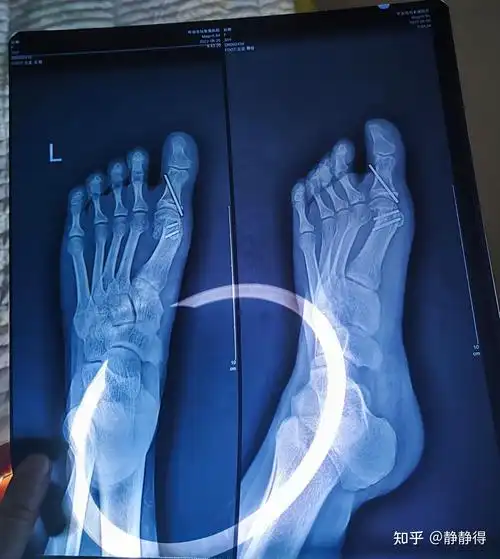

拇外翻(大脚骨)截骨手术后半年 - 知乎